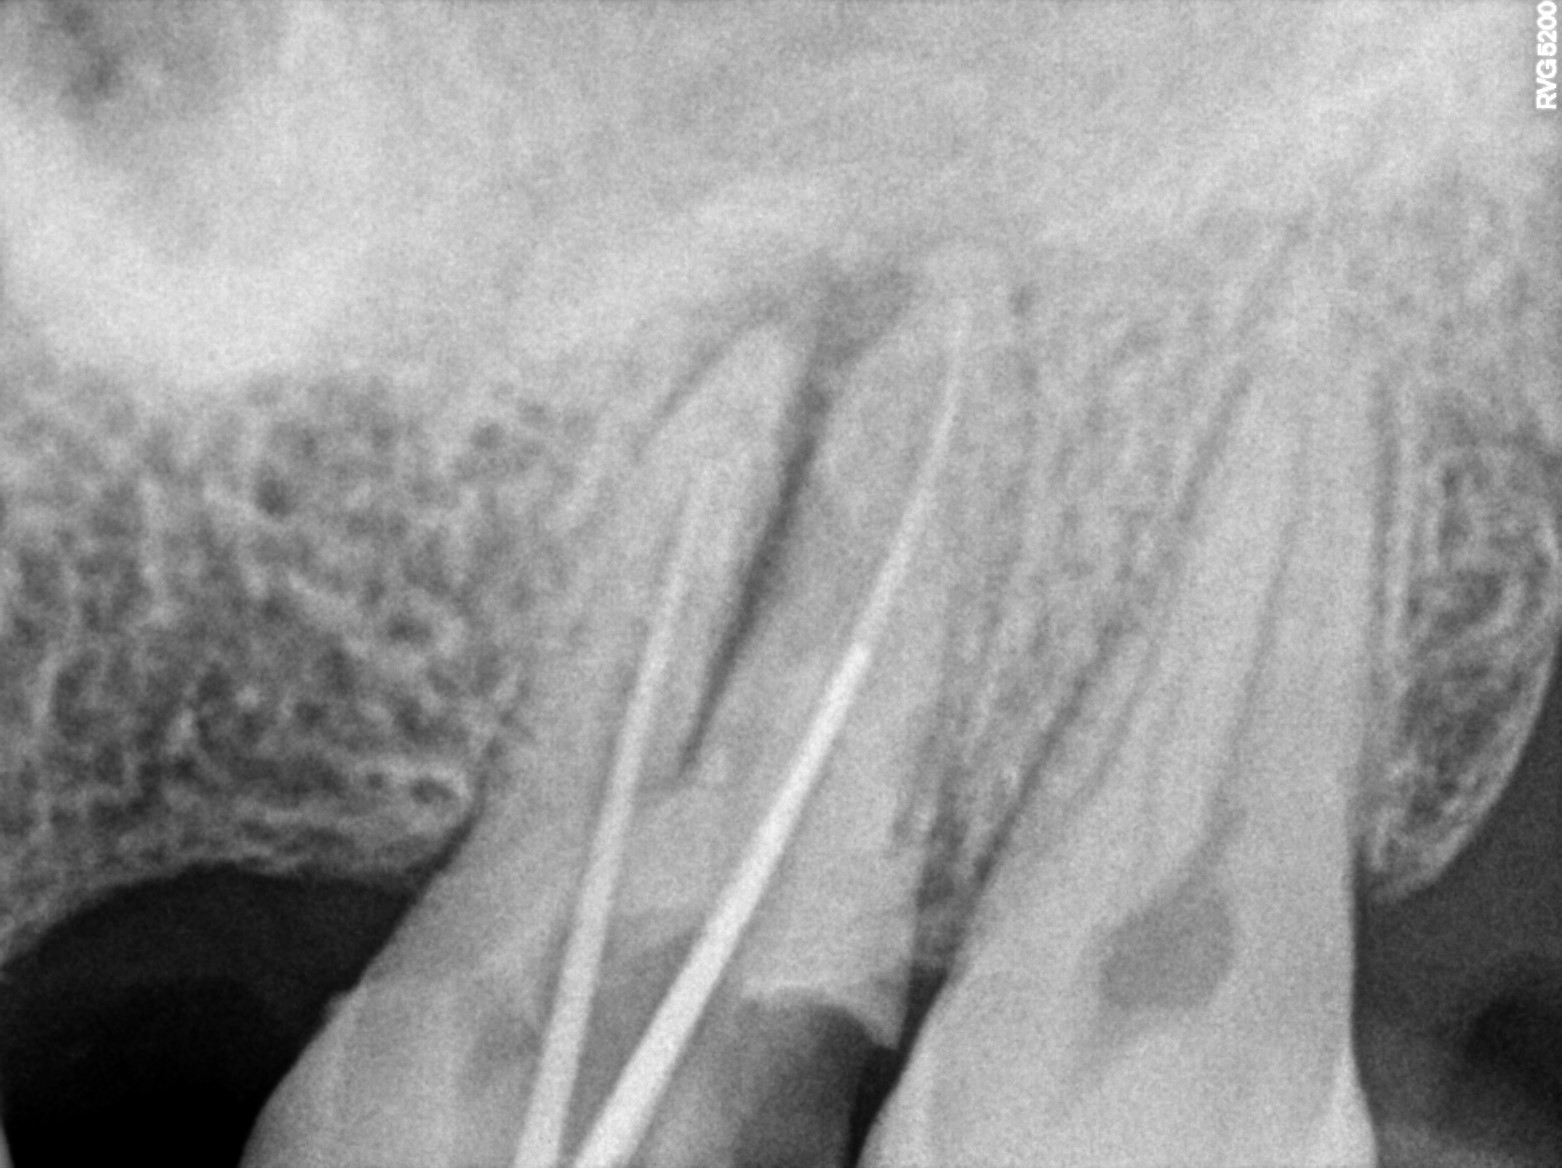

Dental Radiographs FHIR: DocumentReference · LOINC 24641-7

xray_1773504556_0.jpg

24641-7